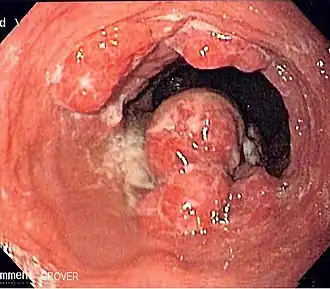

Cánceres de boca, esófago, faringe y laringe

El consumo de alcohol en cualquier cantidad es un factor de riesgo para los cánceres de boca, esófago, faringe y laringe. El Instituto Nacional del Cáncer de EE. UU. afirma que "beber alcohol aumenta el riesgo de cáncer de boca, esófago, faringe, laringe e hígado en hombres y mujeres, ... En general, los riesgos aumentan por encima de la línea de base con cualquier ingesta de alcohol (leve;<2 copas de vino a la semana) y aumenta significativamente con la ingesta moderada de alcohol (una copa de vino al día) con el mayor riesgo en aquellos con más de 7 copas de vino a la semana. (Una copa se define como 12 onzas (355 ml) de cerveza normal, 5 onzas (148 ml) de vino o 1,5 onzas (45 ml) de licor de 80 grados). ... Además, consumir alcohol con tabaco es más arriesgado que hacerlo solo, porque aumenta aún más las probabilidades de contraer cáncer de boca, garganta y esófago".[43] Las Guías Alimentarias para los Estadounidenses 2010 del gobierno federal definen el consumo moderado de alcohol como hasta una bebida al día para las mujeres y hasta dos bebidas al día para los hombres. El consumo excesivo de alcohol se define como más de tres copas al día o más de siete copas a la semana en el caso de las mujeres, y más de cuatro copas al día o más de 14 copas a la semana en el caso de los hombres.

El Consorcio Internacional de Epidemiología del Cáncer de Cabeza y Cuello (INHANCE) coordinó un metaestudio sobre la cuestión.[44] Un estudio que analizaba el cáncer de laringe y el tipo de bebida concluyó: "Este estudio indica, por tanto, que en la población italiana caracterizada por el consumo frecuente de vino, el vino es la bebida más fuertemente relacionada con el riesgo de cáncer de laringe."[45]

Una revisión de la literatura epidemiológica publicada entre 1966 y 2006 concluyó que:

- El riesgo de cáncer de esófago casi se duplicó en los dos primeros años tras dejar el alcohol, un aumento brusco que puede deberse a que algunas personas sólo dejan de beber cuando ya presentan síntomas de la enfermedad. Sin embargo, el riesgo disminuyó después de forma rápida y significativa tras periodos de abstinencia más prolongados.

- El riesgo de cáncer de cabeza y cuello solo se redujo significativamente después de 10 años de suspensión.

- Después de más de 20 años de dejar el alcohol, los riesgos de ambos cánceres fueron similares a los observados en personas que nunca bebieron alcohol.[46][47]

Un estudio concluyó que por cada bebida adicional consumida regularmente por día, la incidencia de cáncer de cavidad oral y faringe aumenta en 1 por 1000. La incidencia de cánceres de esófago y laringe aumenta en un 0,7 por 1000.[42]

Un estudio de 2008 sugiere que el acetaldehído (un producto de descomposición del alcohol) está implicado en el cáncer oral.[48][49]